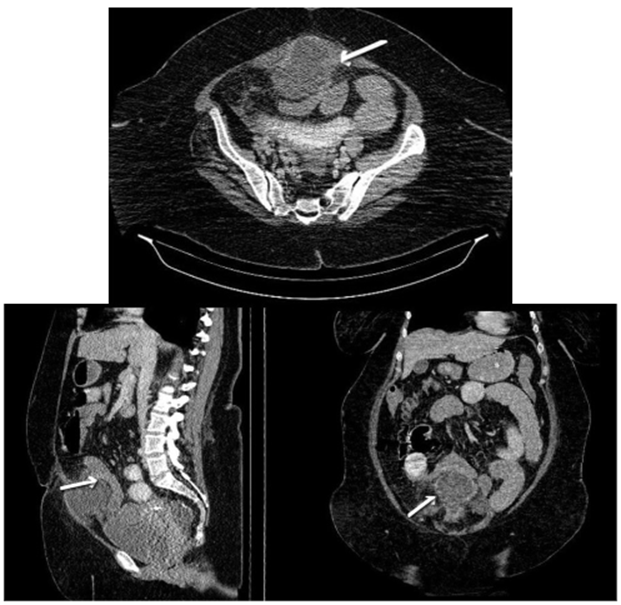

Al ingreso, presentó aumento de la intensidad de dolor, asociado a múltiples episodios eméticos de contenido alimentario y deposiciones diarreicas, por lo que se indicó una (TC) tomografía computarizada de abdomen con contraste, con reporte de remanente del uraco abscedado que condicionaba obstrucción intestinal, por compresión extrínseca de un asa delgada (figura 1).

En caso de que los hallazgos identificados en ultrasonido no sean concluyentes o se tenga sospecha de malignidad, se recomienda la TC como imagen de segunda opción 7,11. La tomografía logra identificar con mayor facilidad el tipo de anomalía, en caso de un absceso, se puede visualizar una estructura de forma cónica, localizada posterior al músculo recto abdominal, con cambios inflamatorios de la grasa mesentérica 2,10. Además, permite evaluar las estructuras y órganos adyacentes con el fin de descartar otras patologías abdomino-pélvicas 12.